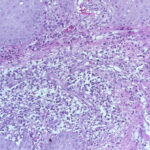

The histopathologic picture in nontuberculosis mycobacterioses is just as variable as the clinical picture and may present nonspecific acute and chronic inflammation, suppuration and abscess formation, or tuberculoid granulomas with or without caseation . In some instances, both tissue reactions occur concurrently. The presence or absence of acid-fast bacilli depends on the tissue reaction. In suppurative lesions, numerous acidfast bacilli often can be found. |

Severely immunocompromised patients, such as those with HIV infection, have a very high prevalence of M. aviumintracellulare bacteremia , and many show one or more cutaneous papules and nodules . Steroid therapy also predisposes to skin lesions. The histology may be granulomatous or mixed acute and chronic inflammatory, as with tuberculosis . Sometimes, there is a histology resembling that of lepromatous leprosy .Macrophages contain large numbers of bacilli without necrosis, and a spindle cell transformation of macrophages, forming a histoid-like lesion (as in leprosy), can occur . |

Histopathology. Early lesions no more than 2 or 3 months old show a nonspecific inflammatory infiltrate composed of neutrophils, monocytes, and macrophages. In lesions about 4 months old, a few multinucleated giant cells and a few small epithelioid cell granulomas usually are present, and in lesions 6 months old or older, typical tubercles or tuberculoid structures may be seen (126). Areas of necrosis are only occasionally present in the centers of the granulomas. The epidermis often shows marked hyperkeratosis with an acute inflammatory infiltrate and ulceration . |

Acid-fast bacilli usually can be identified in histologic sections of early lesions that show a nonspecific inflammatory infiltrate. In contrast, tuberculoid granulomas generally no longer show acid-fast organisms unless areas of central necrosis are present. Although primary lesions usually require a few months for the formation of tuberculoid granulomas, the sporotrichoid nodules that arise later show tuberculoid granulomas and a lack of acidfast bacilli even when they have been present for only a few weeks. |

Histopathology. The infection begins as a subcutaneous nodule exhibiting "ghost" ischemic-type dermal collagen and fat necrosis with deposition of fibrin and hematoxyphilic extracellular clumps of mycobacteria. Ulceration proceeds as the epidermis loses its vascular supply. Ziehl-Neelsen stains reveal vast numbers of acid-fast bacilli in the necrotic fat ; their distribution is often irregular. A variable degree of neutrophil infiltration and thrombosis of vessels are also observed. In time, a nonspecific granulation tissue or a granulomatous reaction commences from the depth and sides of the ulcer; healing and re-epithelialization take place with considerable scarring. Acid-fast bacilli decline rapidly in number during healing . The histopathologic case definition for Buruli ulcer, useful for research studies, is (a) the typical pattern of infarctivelike necrosis of deep dermal collagen and fat and (ideally, but not always found in limited samples) (b) nearby clusters of acid-fast bacilli. |

Healing of Buruli ulcer coincides with development of delayed hypersensitivity to the mycobacterium, possibly contingent on the cessation of mycolactone production. In a recent study, expression of cytokines was correlated with the inflammatory response evaluated by histopathology . All of the cases showed extensive necrosis and chronic inflammation. The most important feature correlating with chronicity was considered to be the presence or absence of granulomas coexisting with a mixed proinflammatory/antiinflammatory cytokine balance. Granulomas were absent from relatively early ulcerative lesions, which contained more bacilli and little interferon (IFN}-gamma, suggesting that at this stage of the disease strong suppression of the protective cellular immune response facilitates proliferation of bacilli. When granulomas were present, significantly higher expression of IFN-gamma was seen as well as lower bacillary counts. |